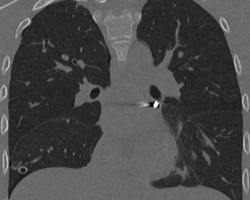

В Детский клинический центр им. Л.М. Рошаля экстренно поступил 16-летний подросток с проникающим ранением грудной клетки от пневматического ружья. Травму он получил во время неосторожной игры с друзьями. В ходе обследования врачи выявили крайне опасное расположение инородного тела в непосредственной близости от сердца: в полости перикарда — наружной оболочки сердца. Состояние пациента требовало немедленного хирургического вмешательства.

— Инородное тело мигрировало в опаснейшую зону — между легочными венами у задней поверхности предсердия. Мы выполнили малоинвазивную операцию со вскрытием перикарда, работая буквально в миллиметрах от жизненно важных структур. Особую сложность представляла необходимость манипулировать инструментами в условиях ограниченного обзора и постоянного движения сердца. В ходе вмешательства нам удалось извлечь инородное тело без единого разреза, — рассказал заведующий отделением детской хирургии №2 Никита Степаненко.